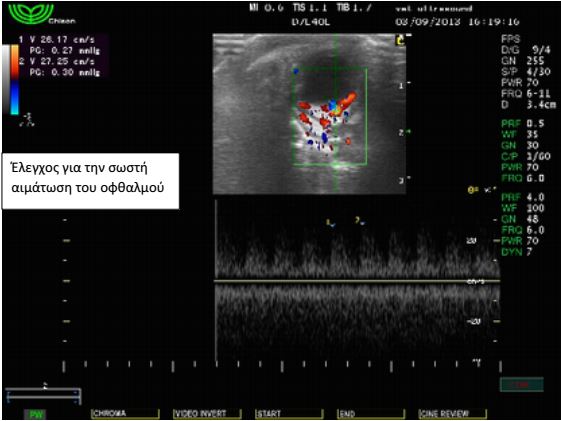

Ασθενής: Γάτα θηλυκή, 2 μηνών, φυλής κοινής ευρωπαϊκής

Προσκομίστηκε με επώδυνη διόγκωση της δεξιάς περιοφθαλμικής

Έγινε υπέρηχος όπου διαπιστώθηκε συγκέντρωση υγρού

αυξημένης ηχογένειας στη περιοχή πίσω από το δεξιό οφθαλμό,

εικόνα συμβατή με οπισθοβολβικό απόστημα. Η αλλοίωση

υποχώρησε τις επόμενες μέρες με αντιβιοθεραπεία και δε

χρειάστηκε να γίνει παρακέντηση.